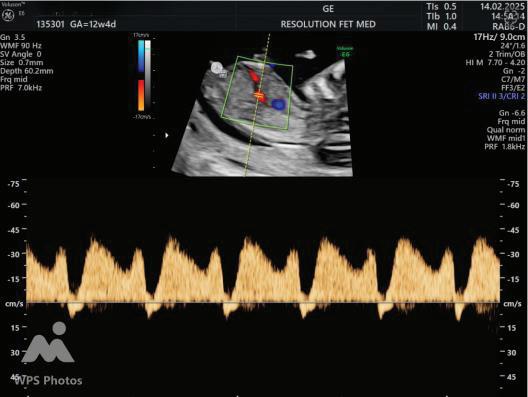

The first trimester— spanning from conception to 13+6 weeks—is no longer considered a “blind phase” of pregnancy. With the evolution of highresolution ultrasound, color Doppler and advanced biochemical screening, this period has transformed into a window of opportunity for early fetal evaluation, risk prediction and preventive strategies.

First-trimester fetal evaluation is not limited to dating the pregnancy or confirming viability—it is the foundation of predictive, preventive, and personalized obstetric care.

2. NUCHAL TRANSLUCENCY (NT) SCAN

• Done @11–13+6 weeks.

• CRL 45–84 mm.

• This is the cornerstone of first trimester screening.

1. NT is the sonographic appearance of subcutaneous accumulation of fluid behind the fetal neck, below the skin in the first trimester of pregnancy.

2. Measured in mid-saggital section only.

3. Measured between 11-14 weeks.

4. CRL between 45-84mm.

5. Magnified to include only head and upper thorax.

6. Fetus should be in neutral position.

7. Demostrate fetus separate from amnion.

8. Measurement should be ON to ON (cross bar of the callipers should be such that it’s hardly visible and merges with white line, not nuchal fluid).

During the scan more than one measurement should be taken and maximum value should be considered.

ADDITIONAL SONOGRAPHIC MARKERS:

A Wave Reversal

MARKER

Ductus Venosus flow

Tricuspid Regurgitation

Tricuspid Regurtitation

SIGNIFICANCE

Reversed a-wave in aneuploidy or cardiac dysfunction

Suggests cardiac abnormality or aneuploidy